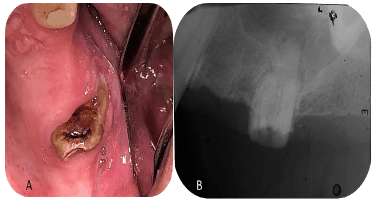

Paciente do sexo masculino comparece ao atendimento odontológico queixando-se de dor em hemiface. Ao exame clínico (imagem A), observou-se dente 26 com cárie extensa e destruição coronária, impossibilitando reabilitação. Na radiografia periapical (imagem B), confirmou-se o diagnóstico e foi indicada exodontia. Considerando os fatores analisados clínica e radiograficamente, assinale a alternativa que apresenta a escolha correta para minimizar complicações.